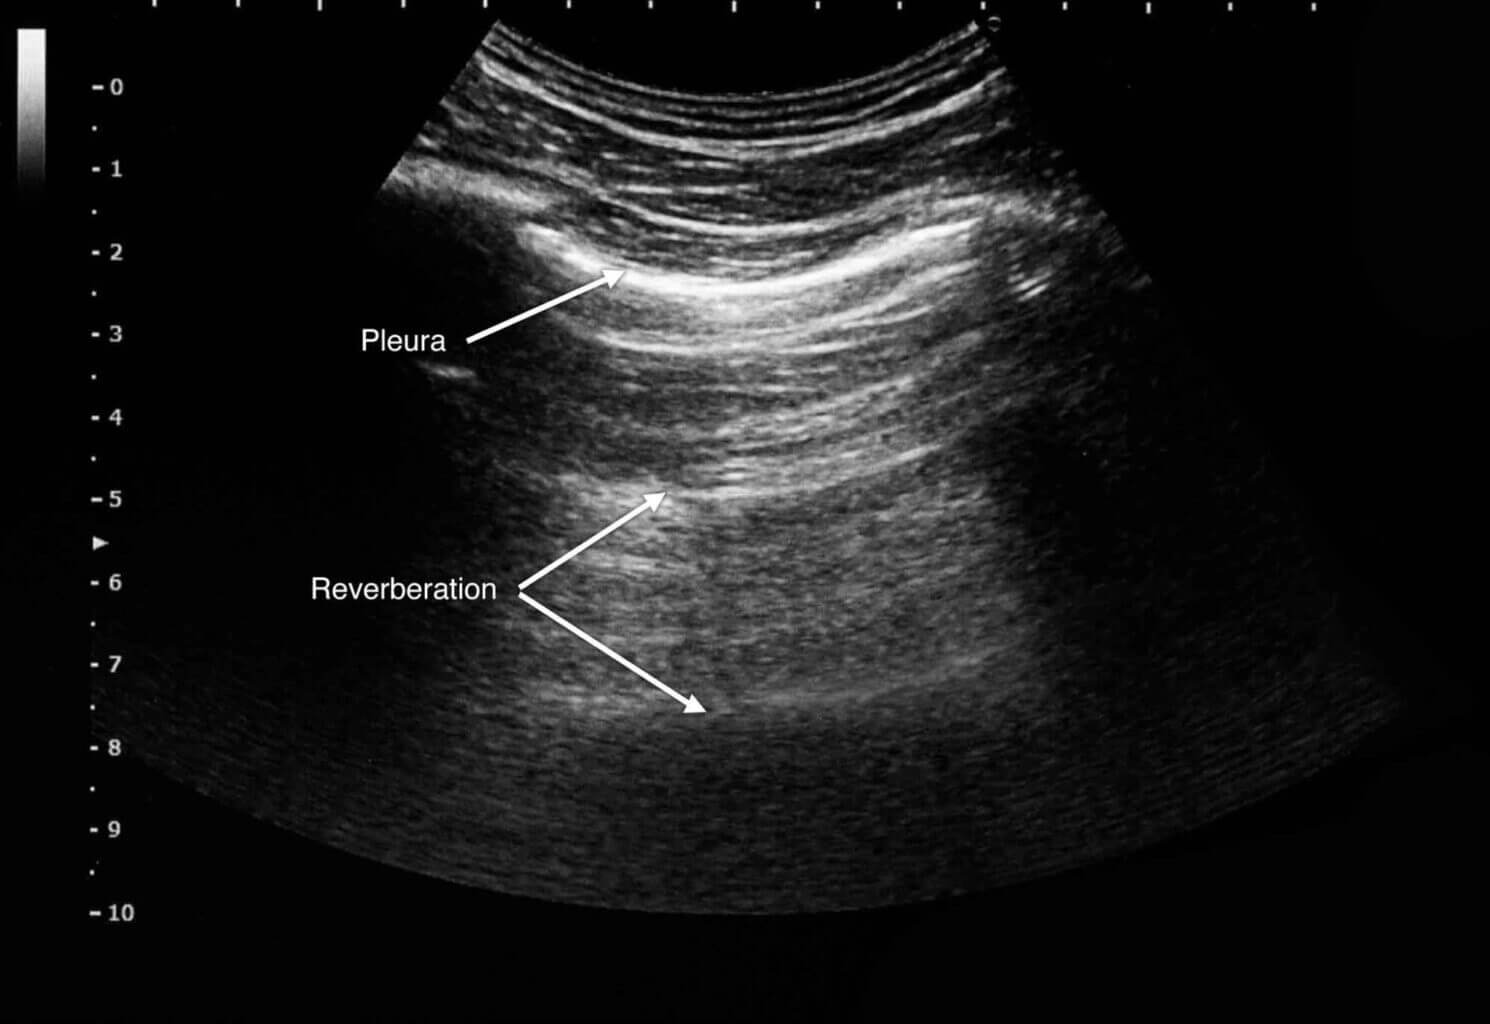

Problema #3: "¡Veo líneas verticales extrañas y brillantes!"

Esto es un Artefacto de Reverberación, a menudo llamado "cola de cometa"."

Se produce cuando el haz de sonido queda atrapado entre dos superficies muy reflectantes y rebota de un lado a otro.